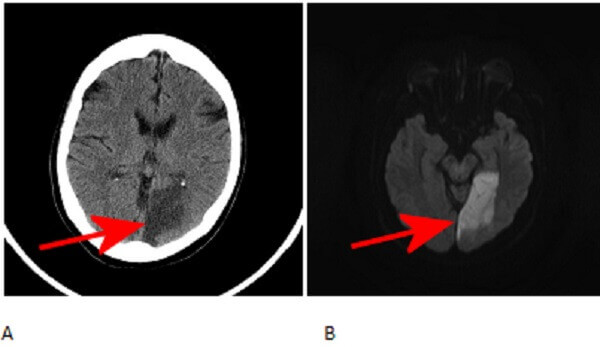

Diagnosis: Acute left posterior cerebral artery stroke.

Figure 1: Red arrows. A. Axial non-contrast head CT demonstrates hypoattenuation of the left medial occipital lobe with loss of grey white differentiation. B and C. Axial diffusion weighted (DWI) and apparent diffusion coefficient (ADC) images demonstrate respectively increased and decreased signal in the occipital cortex.

The paired posterior cerebral arteries supply portions fo the thalamus, lateral ventricle, midbrain occipital and inferomedial temporal lobes. Patients with acute PCA territory infarcts typically experience visual symptoms which can range from honomymous hemianopsia to cortical blindness depending on the extent of the stroke.